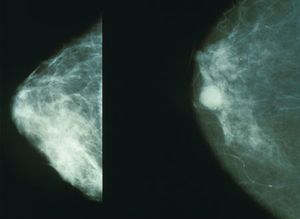

تصوير الثدي Mammography تقنية تستخدم الأشعة السينية لتصوير الثدي من الداخل، وهي إحدى الوسائل الفعالة للكشف عن سرطان الثدي. يتم التقاط الصور باستخدام جهاز أشعة سينية يعمل على ضغط الثدي بين سطحين أملسين. ويتم الضغط على الثدي حتى تتمدد أسنجته فلا يحتاج التصوير إلا لقدر ضئيل من الأشعة السينية. وتقدم هذه العملية التي تعرف باسم الماموجرام (صورة الثدي) صوراً لأنسجة الثدي باللونين الأبيض والأسود، ويقوم بدراستها اختصاصي استخدام الطاقة الإشعاعية.

يطلب الأطباء إجراء تصوير للثدي لتعرف أسباب المشاكل التي تعتريه مثل وجود الكتل، والآلام، ونقرات (رصهات) الجلد، والإخراج غير الطبيعي من الحلمة، ويعرف هذا الإجراء باسم تصوير الثدي التشخيصي. وتظهر كثير من هذه الشذوذات في شكل مجموعة من الرقطات البيضاء الصغيرة تعرف باسم الكلسات ، إلا أن معظم هذه الشذوذات أورام حميدة غير سرطانية. ويتم تعرف الأورام السرطانية من الشكل العام لهذه الشذوذات. فالكتلة السرطانية تكون غير منتظمة الشكل وتفتقر إلى حدود واضحة المعالم. ولكن فإن من الضروري إجراء فحوصات والتقاط صور إضافية للتأكد من وجود الورم السرطاني.